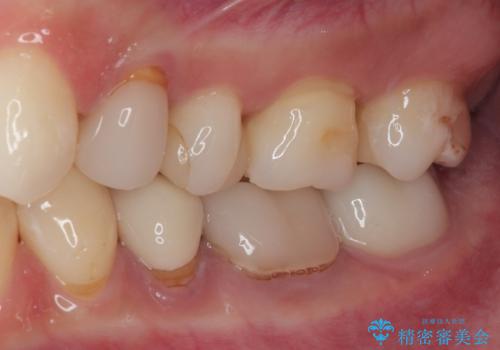

詰め物が欠けたのでやり替えたい セラミックインレー修復

歯と歯茎の間に圧排糸と言われる糸を入れてシリコーン印象材にて精密な型どりをしました。

セラミックインレーの装着時には、唾液の侵入を防ぐために、ラバーダム防湿を行いました。